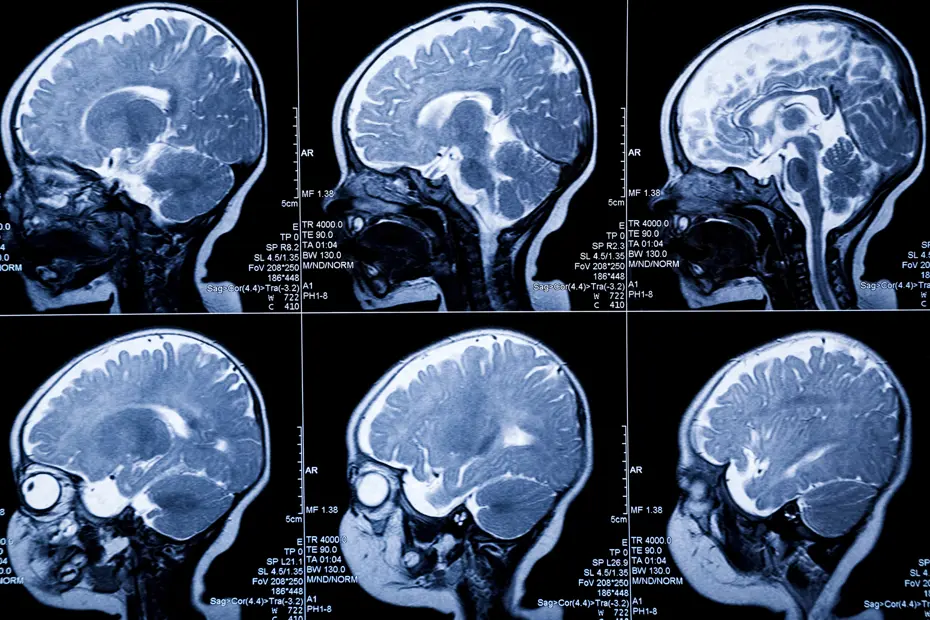

İngiltere’nin Cambridge Üniversitesi uzmanları, yenidoğanların beyinlerini yüksek hassasiyetle görüntülemek için yeni bir teknoloji geliştirdi.

“Theo” adlı üç haftalık bebek üzerinde test edilen başlık, yüzücü bonesini andırıyor. Ultrason ve optik tomografi teknolojileriye donatılan başlık ile bebeklerin beynindeki oksijen seviyesi büyük bir hassasiyetle takip edilebiliyor.

“FUSION” adı verilen teknoloji sayesinde yenidoğanlarda oluşması muhtemel beyin hasarı erkenden tespit edilebilecek.